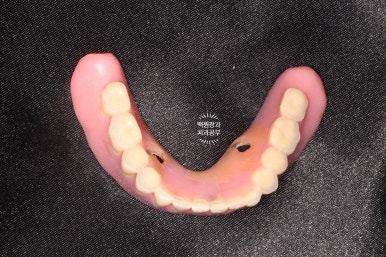

이번에 새로 제작된 틀니입니다.

왼쪽이 위턱 오른쪽이 아래턱.. 잘 모르시겠죠?

왼쪽이 위턱, 오른쪽이 아래턱입니다.

눈치 빠르신 분은 아셨을텐데요, 아래턱 틀니의 치아가 없는 조직면을 보시면 구멍이 두개 뚫려있어요.

그 부분이 나중에 입 안에 튀어나와있는 금색 부분과 연결될 자리 !!

아래턱 틀니 안쪽면에 이렇게 까만색의 파트를 연결해주면,

입안에 틀니를 장착하실 때 딸깍딸깍 뺐다꼈다를 하실 수 있게 되어요.!!

이 녀석의 이름이 바로 오버덴쳐(overdenture)입니다. :)